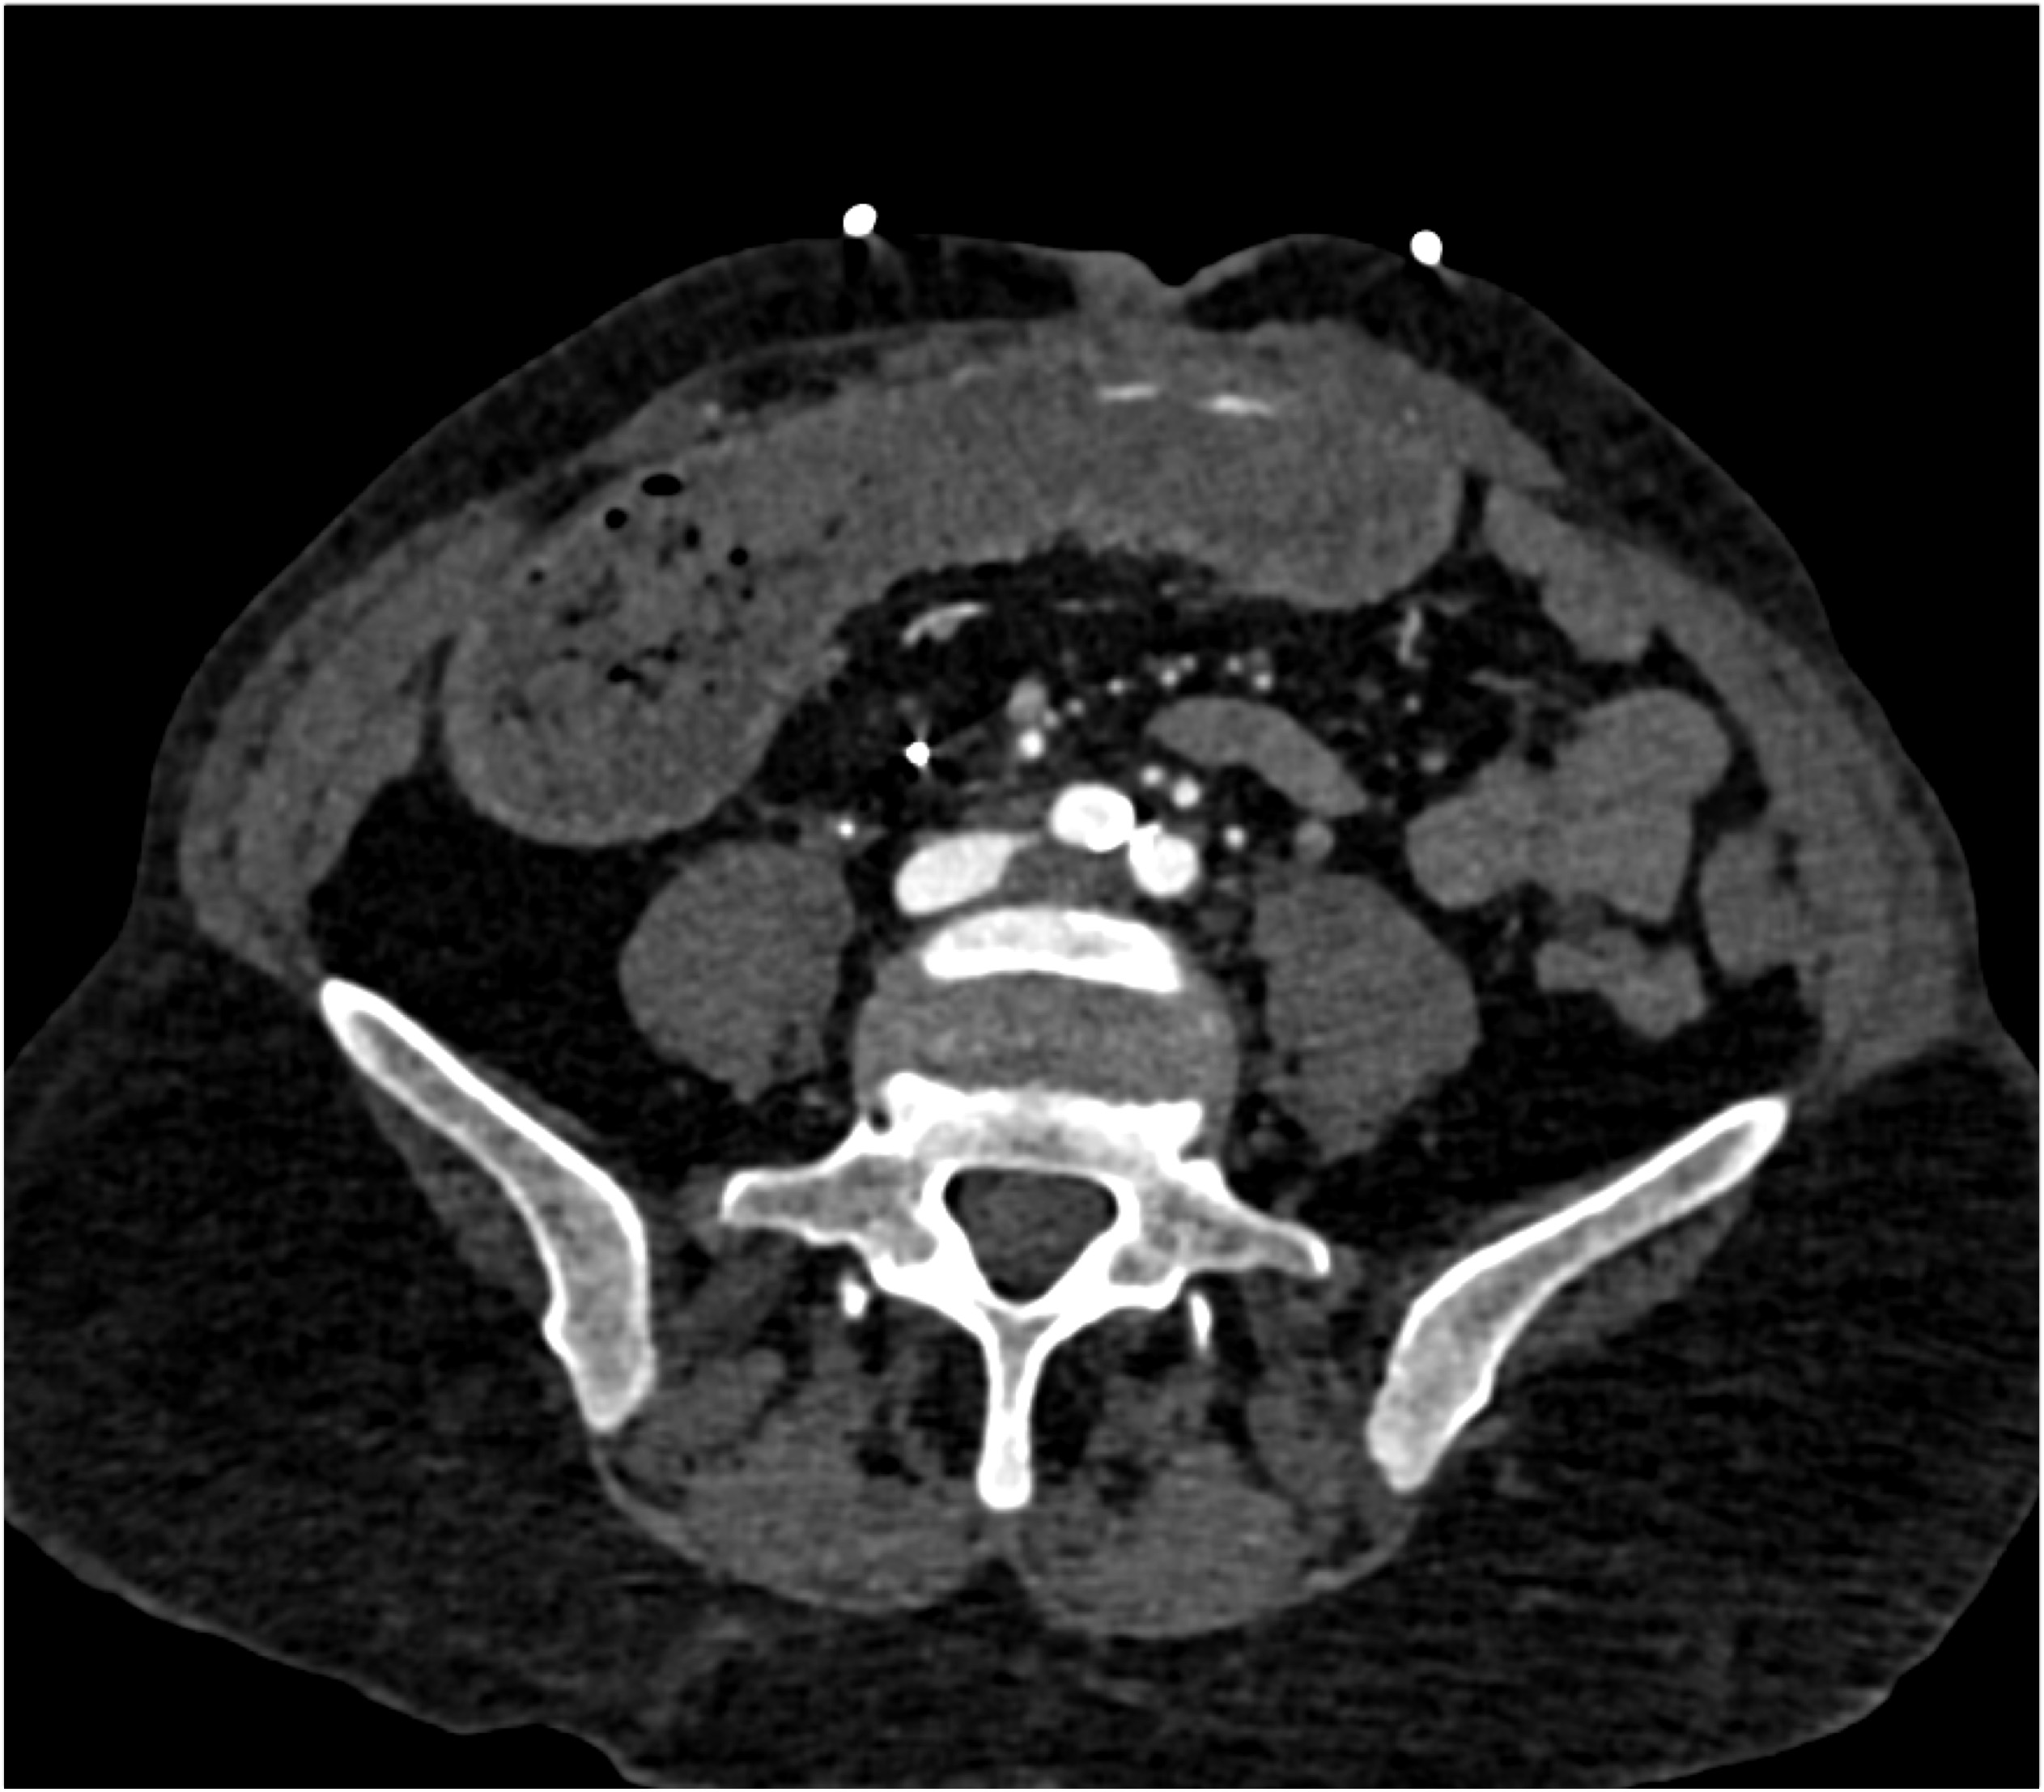

2) In this patient with a palpable right abdominal wall mass the best dx is?

rectus sheath hematoma

lymphoma

desmoid tumor

metastatic renal cell carcinoma